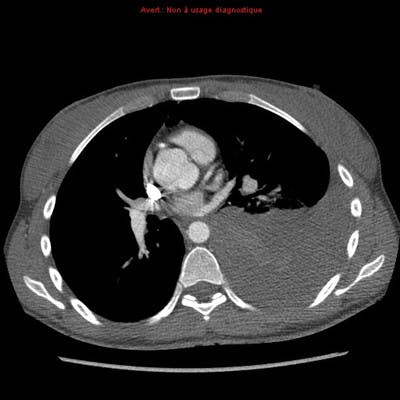

Après globalement pour la différence pneumothorax vs hémothorax, tu as l'exemple du pneumothorax dans le cours où on voit une

hypodensité en noir correspondant à de l'air et en cas d'hémothorax comme c'est du sang tu auras plutôt une zone de couleur

grise, voici l'image d'un hémothorax gauche :

- TDM-Thorax-Axial-Temps-arteriel_400.jpg (17 Kio) Vu 191 fois